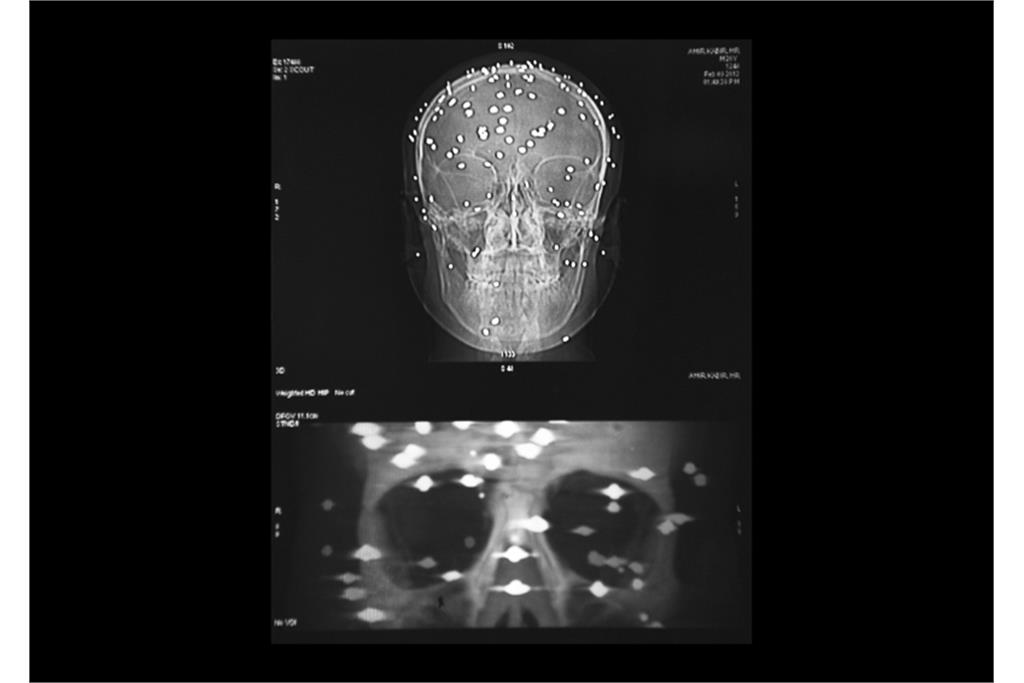

«دره‌ سایه‌ها» مجموعه‌ای از عکس‌ها و اسناد پزشکی در زمینه نقض سیستماتیک حقوق مردمان کشمیر و اعمال شدید‌ترین خشونت‌های دولتی در سرکوب آنها است و نشان دهنده سایه‌ سیاهی که بر دره‌ کشمیر افتاده است و مردمانی که از درون شکسته‌اند. هم‌نشینی بیرون(عکس‌های عادی) و درون (عکس‌های اشعه ایکس)‌ از افراد، تلنگر این فاجعه بر بیننده را دوچندان می‌کند.گویی درد پنهان و آشکار آن‌ها در تاریکی فرو می‌رود و از آن‌ها جز سایه‌ درد و نقطه‌های روشن ترکش‌های داخل بدنشان در عکس‌های اشعه ایکس چیزی باقی نمی‌ماند.